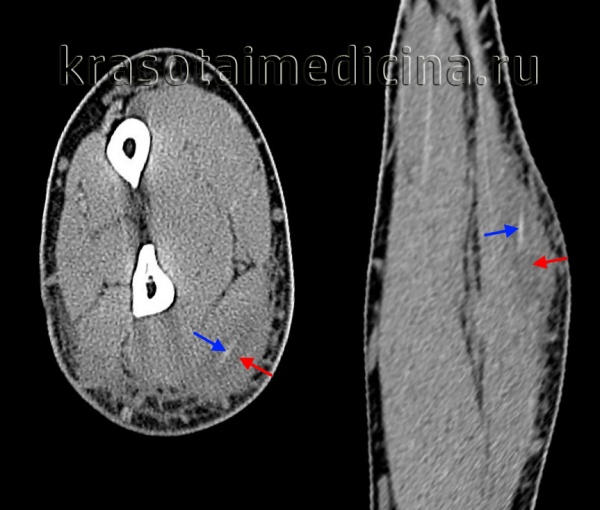

КТ при мастоидите с тромбозом сигмовидного синуса

КТ височных костей. Тотальное снижение пневматизации ячеек сосцевидного отростка с обеих сторон. (фото Вишняков В.Н.)